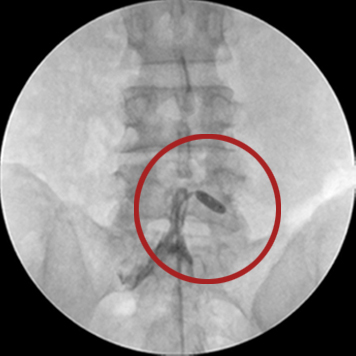

고주파수핵성형술, 플라즈마감압술

직경 2mm 이내의 가느다란 주사바늘을 문제가 생긴 디스크에 삽입하여 고밀도이온화장(플라즈마장)을 쏘아 척추신경을 압박하는 디스크 내의 분자를 분해하고 녹인 후, 수축 응고 시키는 치료법입니다.

고주파 수핵성형술은 전신 디스크가 완전히 파열되지 않거나 아직 나이가 젊고 상태가 수술할 정도로 심각하지 않은 경우 적용됩니다. 문제가 있는 디스크에만 적용하기 때문에 다른 근육과 신경의 손상 위험이 적고 요추관 협착증이나 척추 불안정증이 있는 경우에는 시술하지 못합니다.

□ 이동식 X-ray(C-arm X-ray)로 진행 모습을 실시간으로 확인이 가능해 안전함